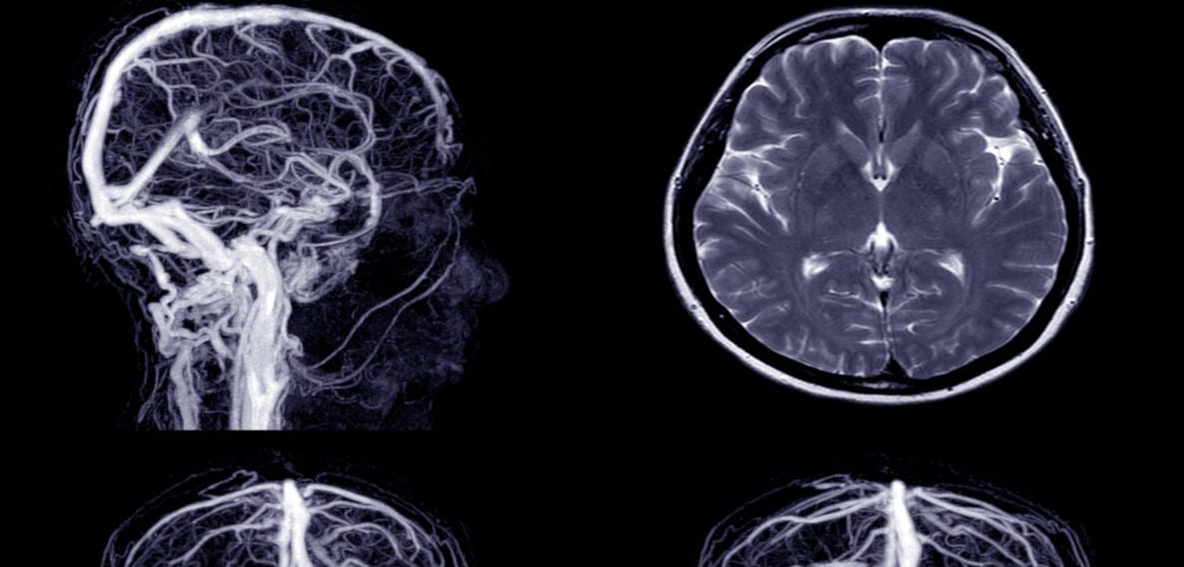

Odmah nakon pojave simptoma, važno je otići u hitnu službu. Ljekari će obaviti potrebne pretrage (CT, MR, krvne analize, EKG) kako bi ustanovili uzrok i spriječili ponovni – i mnogo ozbiljniji – udar.